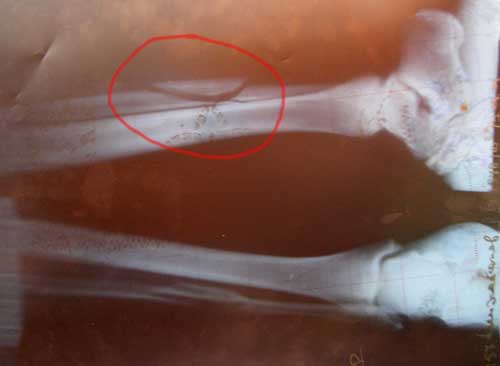

Во втором бою я встречался с сильным бойцом из Шин-киокушина Намигом Насировым (хотя честно скажу, что слабых на турнире не было вообще). Работая с ним сделал несколько сильных лоу и тут же этой ногой крутанул уширо-маваши в голову. Он успел закрыться и я голенью попал ему кажется в локоть. Вот тут это и произошло. Я не знаю как это получилось, но ошеломление было настолько сильным, что в первую секунду я принял звук ломающейся кости за звук чего-то упавшего на татами. Если посмотреть запись, то видно, как остановившись на секунду я растеряно вожу глазами по татами и даже показываю рефери, что у него вроде что-то упало. И только недоумённый взгляд судьи и окрик тренера заставляют меня продолжить бой. Видимо это был шок. Дальше я помню не очень хорошо, как заканчивал бой, как сходил хромая с помоста. Боль была жуткая. В себя пришёл только в руках врача нашей команды Михаила Язовских. Огромное ему спасибо, потому что без его помощи я вряд ли смог продолжить драться дальше. Он так грамотно замотал, заморозил и обезболил травмированное место, и так уверенно убедил меня, что там никак не может быть перелома, что я даже это поверил. Но и потом, когда на следующий день в Москве друзья повезли меня в больницу, где сделали снимок, ни я сам ни окружающие не могли понять, как с такой травмой я провёл ещё четыре боя (снимок прилагается).